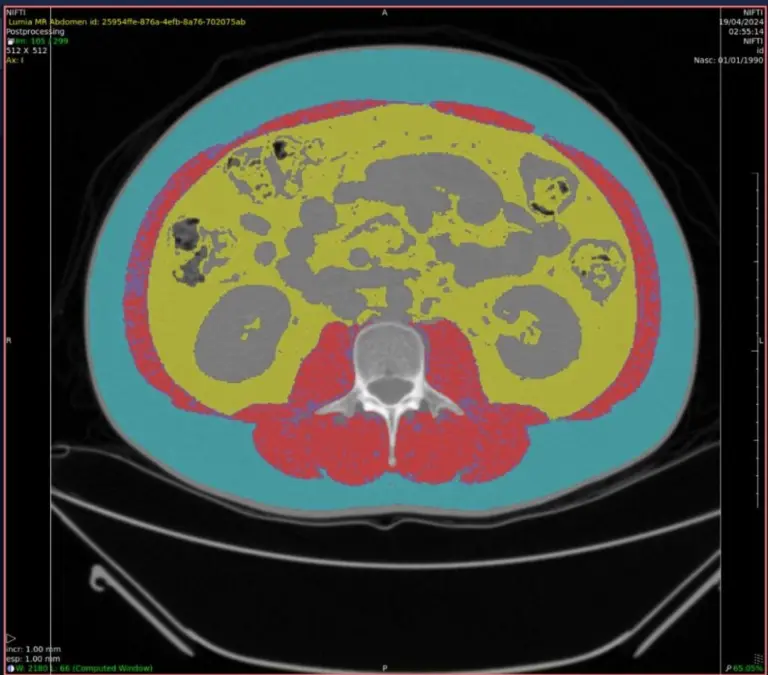

AI for Sarcopenia Calculation

Sarcopenia is defined as a change in skeletal musculature characterized by a reduction in strength and muscle mass secondary to aging, which compromises the individual’s physical performance.

AI tools with this specialty can flag clinical findings and perform an automated measurement of abdominal fat distribution, accompanied by an assessment of muscle mass.